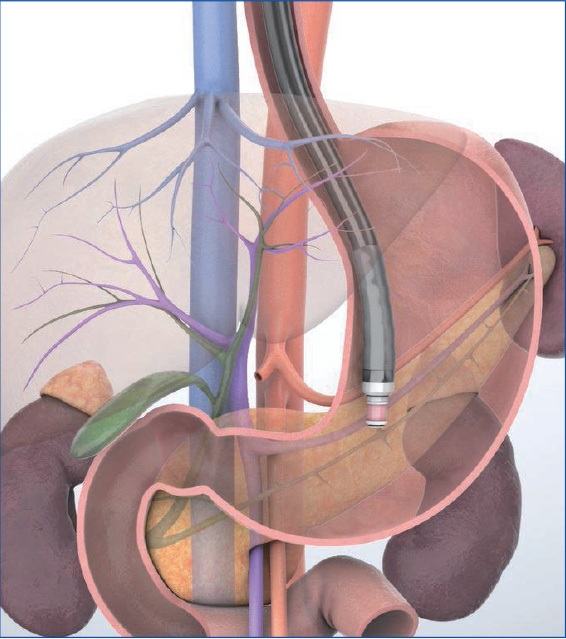

Straighten the scope in the stomach to observe sectional images perpendicular to the scope when viewed from the foot of the patient. To ‘The common method is to first advance the scope to the gastric body or antrum and scan while pulling the scope with the balloon inflated. Another method is to perform continuous scanning while in the “short-scope” position during transduodenal maneuvering. Either way, when the pancreas is visualized, position the pancreas in the six o’clock position on the screen and observe the body and tail of the pancreas and its vicinity while using anatomical features in the surrounding area as landmarks.

Slowly pull the scope from the gastric body or antrum to straighten the scope. Then use the splenic vein as a landmark to observe the pancreatic body.